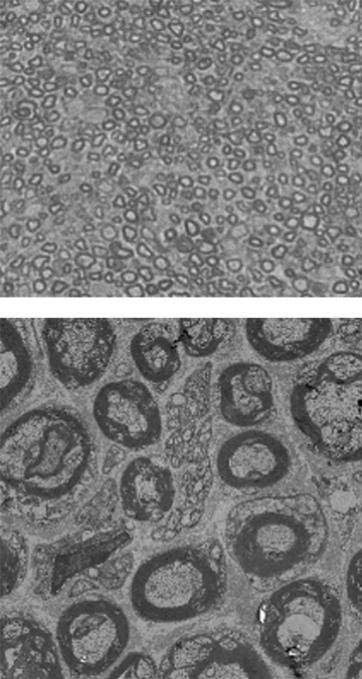

정상 쥐모델

-

샤르코-마리-투스 쥐모델

EN001 투여

신경을 감싸고 있는 수초(지질단백)은 사진에서 짙은 회색으로 표시가 되는데

정상 쥐모델보다 CMT 쥐모델에서 수초의 두께가 얇아지고 형태가 불안정한 것을 볼 수 있습니다.

그러나 EN001을 샤르코-마리-투스 쥐모델에 투여하였을 때, 수초의 두께가 두꺼워지고 형태가 건강해진 것을 관찰하였습니다.